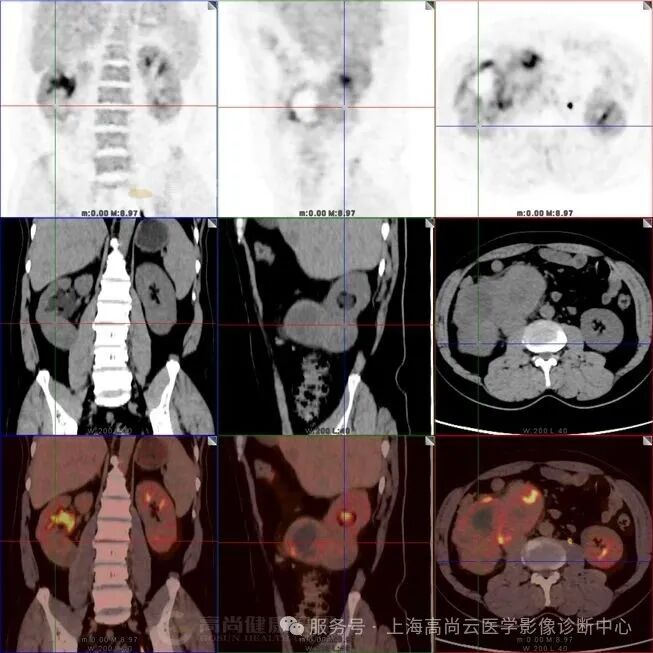

图一:PET 全身 MIP 图;箭头所指为腹部 FDG 摄取增高灶。

图二:右侧腹腔大片不均匀 FDG 摄取异常增高影,SUVmax 约介于 3.3~12.0 之间,范围约 12.7 cm×7.1 cm×13.5 cm,CT 于上述部位见巨大软组织占位,分叶状,边界清晰,其中见多个低密度影,CT 值介于 17.0 Hu~44.0 Hu 之间,病灶推挤邻近下腔静脉,推挤邻近胰头部、十二指肠,累及右肾下极、右侧输尿管上段及右侧腰大肌

图三:腹腔肿块内 FDG 摄取最高部位,SUVmax 约 12.0。

图四:肿块与腰大肌分界不清,提示侵犯。

图五:肿块内见多发低密度区,该局部 FDG 摄取降低。

图六:肿块与肾脏下极实质分界不清,提示肾脏侵犯。

图 7-9:肝实质内多发低密度灶,FDG 摄取轻度增高,SUVmax2.9,延迟显像后 SUVmax 约 4.1